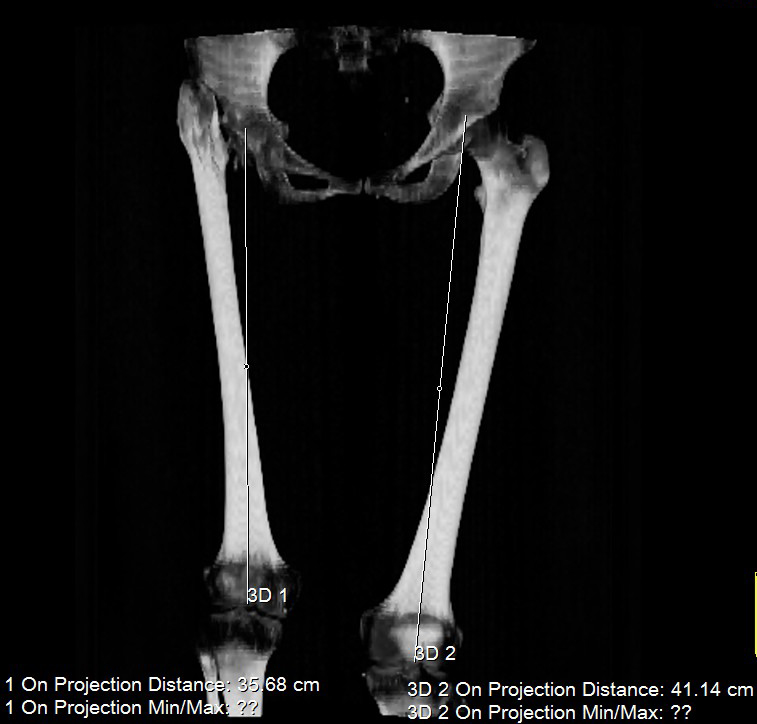

Поскольку основная жалоба на укорочение конечности, то я ей предложил удлинить голень. Величину удлинения обсудили - в пределах 4 см.

>В настоящее время: жалобы на укорочение конечности. Собирается рожать

>детей. Конечность укорочена на 7 см. Функция в правом тазобедренном

>суставе полная! Коллеги, Ваше мнение по поводу лечения?